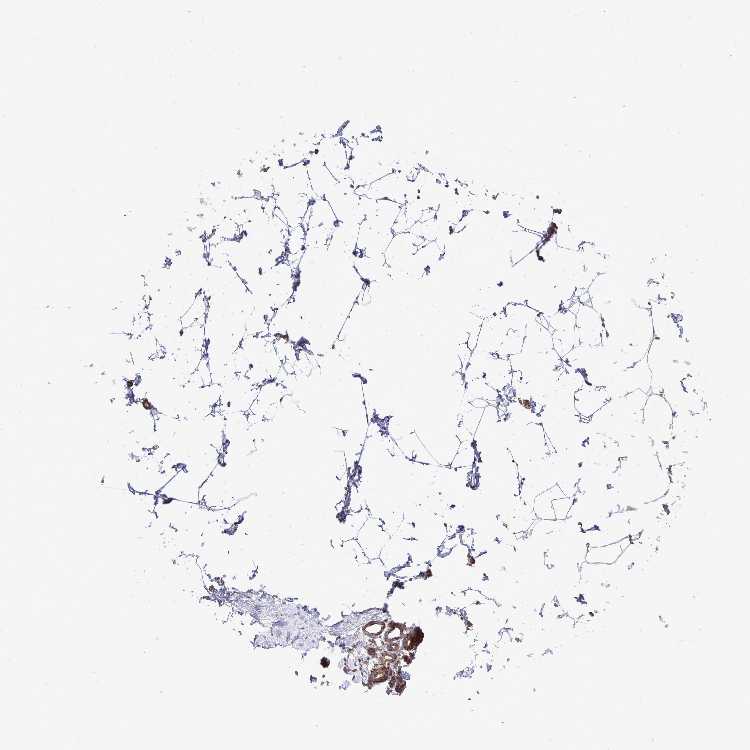

BREAST - Antibody stainingi

Antibody staining in the annotated cell types in the current human tissue is reported as not detected, low, medium, or high, based on conventional immunohistochemistry profiling in selected tissues. This score is based on the combination of the staining intensity and fraction of stained cells.

Each image is clickable and will lead to virtual microscopy that enables deeper exploration of all samples and also displays staining intensity scores, fraction scores and subcellular localization as well as patient and tissue information for each sample.

Antibody HPA050118Antibody HPA056084Antibody CAB012444

Adipocytes Not detectedNot detectedNot detected

Glandular cells MediumMediumHigh

Myoepithelial cells MediumLowHigh